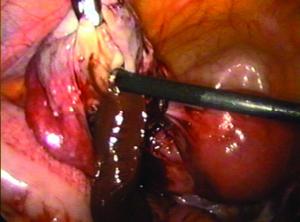

卵巢黃素瘤屬於生理性。腫瘤扭轉、壞死或破裂後,出血不能控制者,行卵巢切除;較大者可在B超介入下或腹腔鏡下穿刺抽液。在不能明確診斷,但患者腫瘤增長迅速時,可行剖腹探查手術,卵巢黃素瘤常為雙側性,多房性,囊壁薄,表面光滑,張力大,囊液淡黃色。

卵巢黃素瘤正常妊娠合併卵巢黃素瘤很少發生,其發生可能與卵巢對HCG敏感性高有關。若做HCG測定則大於正常值,當肉眼觀難以做出決定時應取部分組織送快速病理切片。若診為卵巢黃素瘤應儘量保留正常卵巢組織。婦產科醫生在術中必須熟練分辨卵巢黃素瘤的上述肉眼特性,儘量避免術中疑卵巢惡性腫瘤行雙側附屬檔案切除術。有的醫生曾因過失在剖宮產時為卵巢黃素瘤患者切除雙卵巢,但是這種做法嚴重影響患者生活質量。